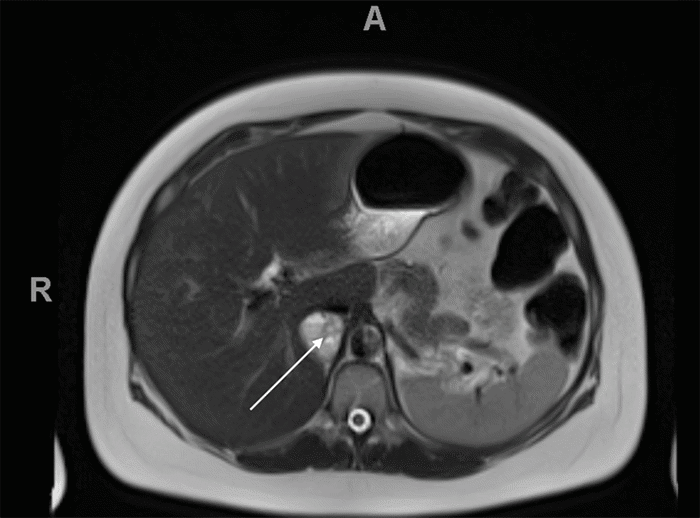

Biochemical testing at 31 weeks gestation revealed significantly elevated urine normetanephrine (4630 mcg/24 hour; normal 35-482 mcg/24 hour) and total metanephrine (4786 mcg/24 hour; normal 115-695 mcg/24 hour) levels, while catecholamine levels were within normal range. Subsequent magnetic resonance imaging (MRI) of the chest, abdomen, and pelvis revealed a 3.4 × 3.6 × 3.9 cm heterogenous mass in the right adrenal gland (Figures 1-3), consistent with pheochromocytoma.

Figure 2. Sagittal View of T2-Weighted MRI (arrow indicating pheochromocytoma). Published With Permission